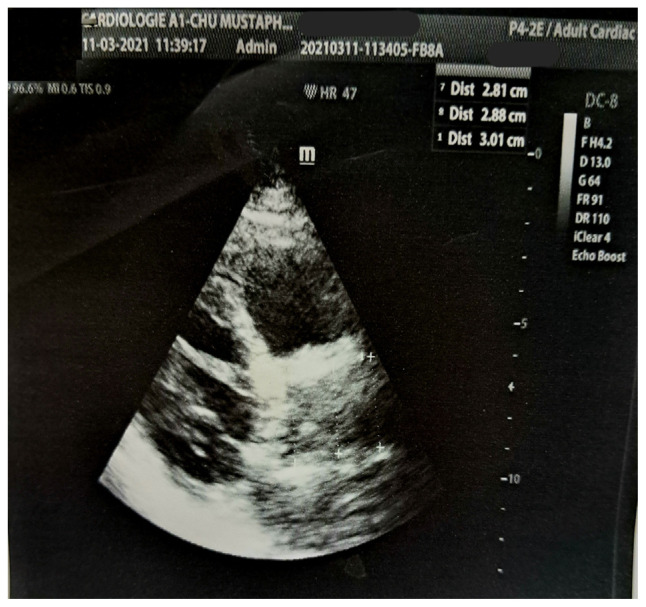

Unexpected porcelain aorta is a real challenge to safely completing aortic valve replacement combined with coronary artery surgery. This condition often leads to an aborted sternotomy in the hope of performing transcatheter procedures, the feasibility of which may be hampered by anatomical considerations. We report the case of a 71-year old man with history of hypertension, type 2 diabetes mellitus and chronic kidney disease, which was referred for severe aortic valve stenosis and severe coronary artery disease. He benefited from an anaortic off-pump coronary surgery and clampless aortic valve replacement under hypothermic circulatory arrest to overcome an unexpected porcelain aorta.